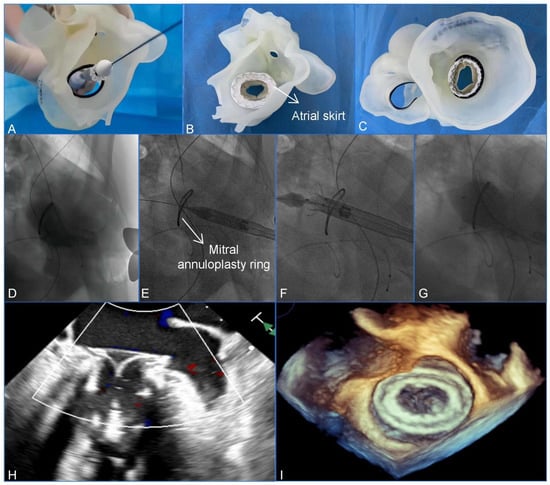

Clinically, 3D printing is essential for assisting with the management of complex cardiac anatomies. Wang et al. utilized a patient-specific 3D-printed model to guide a transcatheter mitral valve-in-ring (TMViR) replacement, which assisted with valve sizing and anticipating intraoperative complications. This study confirms new clinical directions, such as endovascular navigation enabled through the use of 3D-printed models [contribution 8] (Figure 2).

Figure 2.

A preoperative assessment and simulation of the main procedural steps for a transcatheter mitral valve-in-ring replacement on patient-specific 3D-printed models. (A) The adjustment of the coaxiality and the release position. (B,C) The stent was fully unfolded and observed in the left atrial and the ventricular views. (D–G) The main steps of the procedure. (D) Fluoroscopy revealed severe mitral regurgitation. (E) The delivery system was advanced via the transapical approach. (F) The initial release of the stent. (G–I) After the stent was fully released, fluoroscopy and transesophageal echocardiography revealed that the bioprosthesis was in a stable position and functioning well without paravalvular leakage. Reprinted with permission under an open access protocol from Wang et al. [contribution 8].